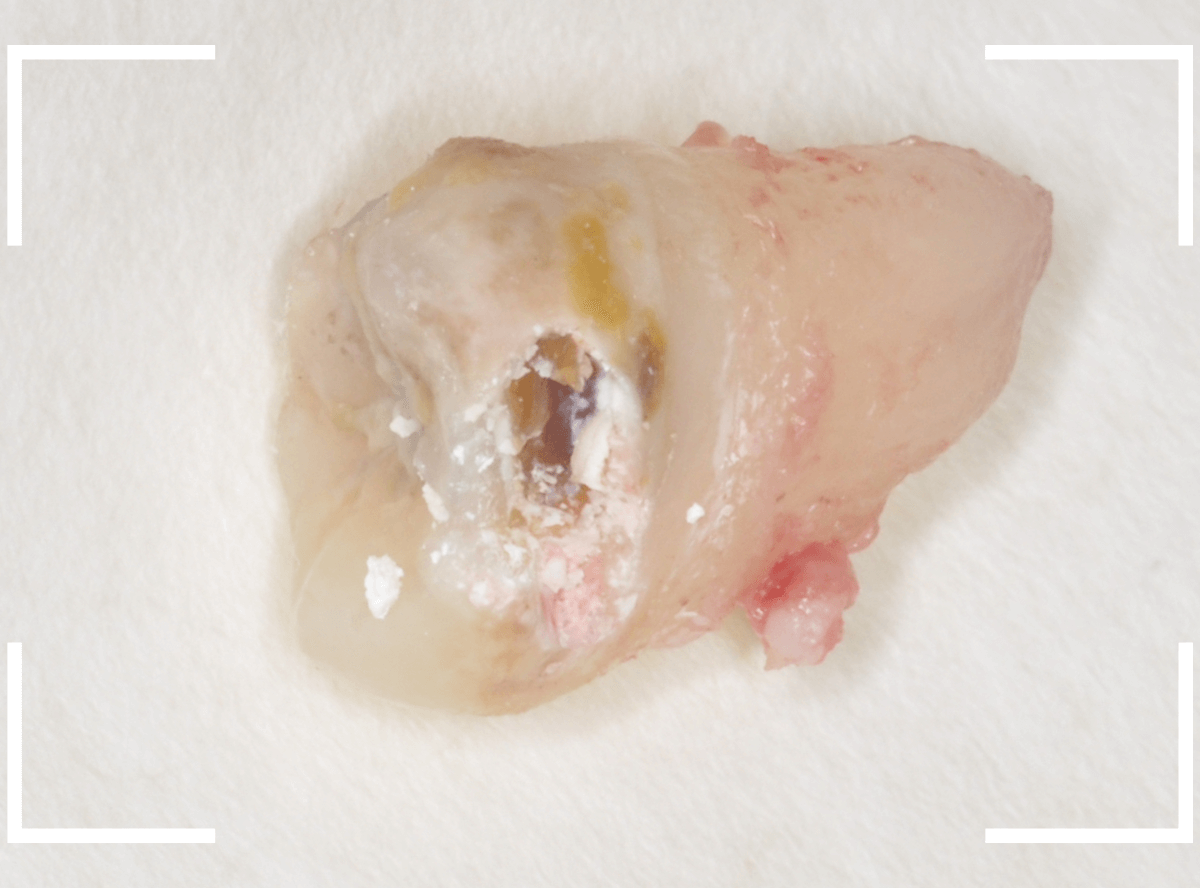

ここでは、比較的簡単なおやしらずの抜歯の例を中心にご紹介します。

このようなおやしらず、あなたはありませんか?